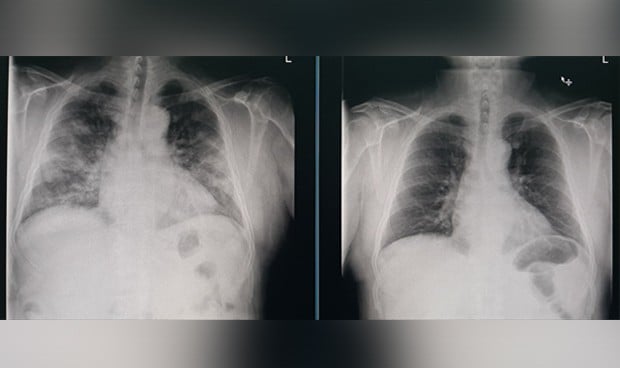

A su vez, este residente ofrece dos radiografías de un mismo paciente para que se vean las diferencias entre su estado normal y con neumonía bilateral causada por el Covid-19. La neumonía es uno de los síntomas graves que provoca el SARS-CoV-2 y de hecho, puede llegar a dejar secuelas en los pacientes.